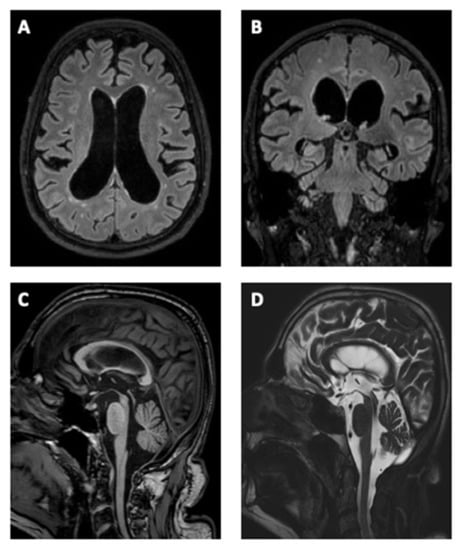

The first examination at our Movement Disorder Center of the 2nd Department of Neurology, Comenius University and University Hospital Bratislava in May 2018 showed akinetic-rigid predominantly axial symmetric parkinsonism, impairment of saccades, and smooth pursuit eye movements mainly in the vertical direction with persevered oculocephalic reflex, hypokinetic dysarthria, dysexecutive syndrome, severe postural instability, and parkinsonian gait with a freezing of gait and falls (Supplementary Video S1). The patient was without any pyramidal signs, bulbar symptoms, sensorial cortical deficits, cerebellar signs, or autonomic dysfunction (except urinary incontinence which appeared after the first year after the onset of the parkinsonian symptoms). At this time, the patient was only able to walk unassisted when at home. The patient was treated with 0.18 mg pramipexole, three times a day (TID) and levodopa/carbidopa/entacapone 50/12.5/200 mg, four times a day (QID), without improvement of symptoms. Static posturography documented severe postural impairment and a positive Romberg test with backward falls. His posture was characterized by an increased amplitude of body sways. A neuropsychological examination revealed mild dementia, predominantly presenting as severe deficits of visuo-constructive, executive functions, with worsened performance in divided and selective attention; memory was globally deteriorated, mostly in the intelligibility and recognition memory (Montreal Cognitive Assessment = 19/30 points, Frontal Assessment Battery = 9/18 points). The patient had mild depression according to the Beck Depression Inventory—II (8/63 points). A brain MRI (magnetic resonance imaging) showed atrophy of the mesencephalon with hummingbird signs and ventriculomegaly. The Evans index was 0.33 and an MRI revealed an aqueduct flow void, disproportionately enlarged subarachnoid spaces, thinning and elevated corpus callosum with a callosal angle of 63°, and T2/Flair hyperintense lesions of white matter (Figure 1). Subsequently, we performed a cerebrospinal fluid (CSF) flowmetry MRI that showed the presence of hyperdynamic circulation through the aqueduct (stroke volume was 124 μL). Furthermore, the patient fulfilled the diagnostic criteria of clinical and MRI evidence for both of the two concurrent diagnoses—PSP (Level 2) and iNPH [1,2,3]. We performed a lumbar tap test with a withdrawal of 40 milliliters of CSF. In the three-meter Timed Up and Go Test, we observed a significant improvement in walking speed 24 h post lumbar puncture (17.5 vs. 13.2 s; Supplementary Video S2). In addition, the patient reported a significant improvement in walking and stability. The CSF examination revealed normal biochemical and cytological findings, with normal hTAU and pTAU181 levels (110.7 pg/mL; 35.1 pg/mL), and reduced Aß42 levels (394.4 pg/mL).

Figure 1. Brain MRI of the typical morphological changes associated with idiopathic normal pressure hydrocephalus and progressive supranuclear palsy. (A) Axial Flair, ventriculomegaly with an Evan’s index of more than 0.3, enlargement of lateral and third ventricles with a widening of the temporal horns, and mild T2 hyperintensities in the periventricular and deep white matter. (B) Coronal Flair, disproportionately enlarged subarachnoid spaces, tight high convexity (narrow sulci and subarachnoid spaces at the vertex and medial/parafalcine region) accompanied by enlargement of the inferior cerebrospinal fluid (CSF) spaces, particularly in the Sylvian fissures. The callosal angle measured at the level of posterior commissure is typically less than 80°. (C) Sagittal T1, midbrain atrophy (penguin or hummingbird sign), thinning and upward bowing of the corpus callosum. (D) Sagittal T2 Drive CSF—midbrain atrophy and strong flow void in the aqueduct of Sylvius.